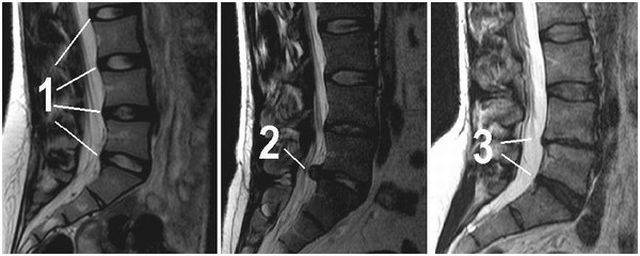

Диагностика и лечение протрузии межпозвоночного диска поясничного отдела осуществляется специалистом на основании осмотра больного и его жалоб. Диагноз подтверждается при помощи МРТ. Магнитно-резонансная томография позволяет выявить характер и стадию патологического процесса при протрузии.

Диагностика и лечение протрузии межпозвоночного диска поясничного отдела осуществляется специалистом на основании осмотра больного и его жалоб. Диагноз подтверждается при помощи МРТ. Магнитно-резонансная томография позволяет выявить характер и стадию патологического процесса при протрузии.

Диагноз устанавливается при помощи проведения процедур КТ или . На полученных снимках врач должен определить место локализации протрузии и её размеры.